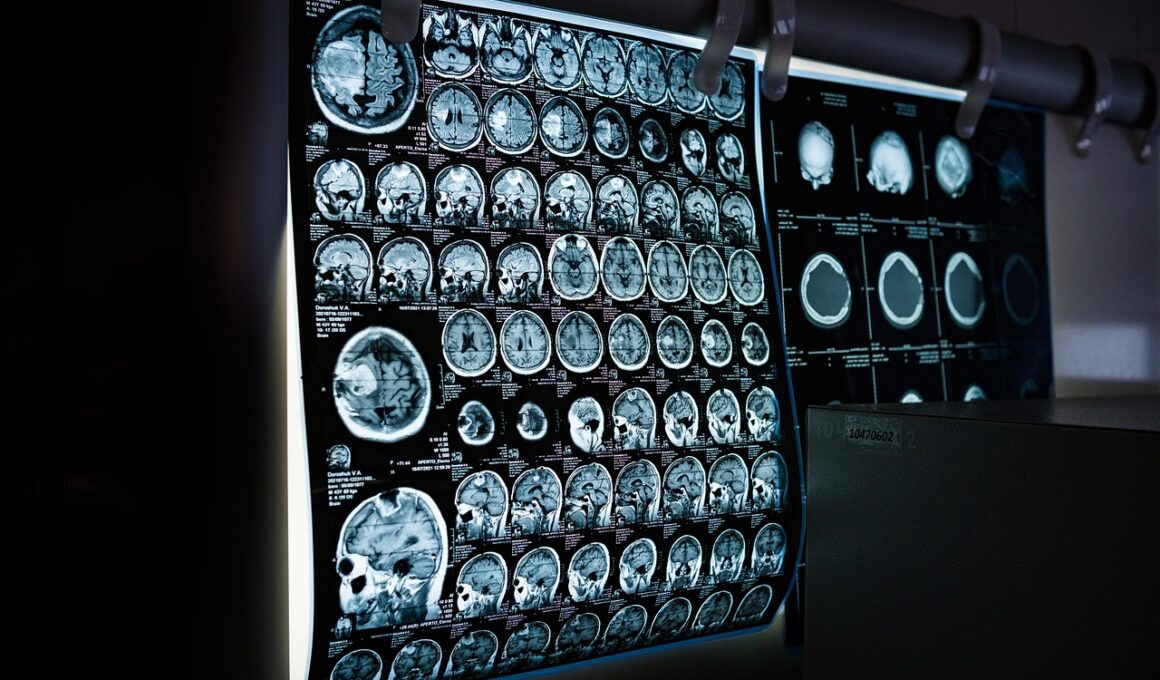

Imaging techniques have revolutionized our understanding of animal reproductive anatomy, providing insights into both the structure and function of reproductive organs. Traditional dissections, while informative, often limit our comprehension of the complex interactions within these systems. Technologies such as ultrasonography, MRI, and CT scans allow us to visualize these organs non-invasively, granting a clearer picture of their morphology and physiology. For instance, ultrasonography is widely used in veterinary medicine to monitor the reproductive cycles of female animals. This technique offers real-time images, revealing essential information about follicle development and ovulation timing. Moreover, the capability to observe these processes aids in better management of breeding programs in various species. Additionally, MRI techniques provide high-resolution images, which help in detecting abnormalities such as tumors or lesions in reproductive tissues. This level of detail equips veterinarians and researchers with the necessary data to make informed decisions regarding treatment. Furthermore, these imaging modalities play a crucial role in education, allowing students and practitioners to visualize complex anatomical structures without invasive procedures. Thus, the integration of imaging in this field significantly enhances our understanding of animal reproductive anatomy.